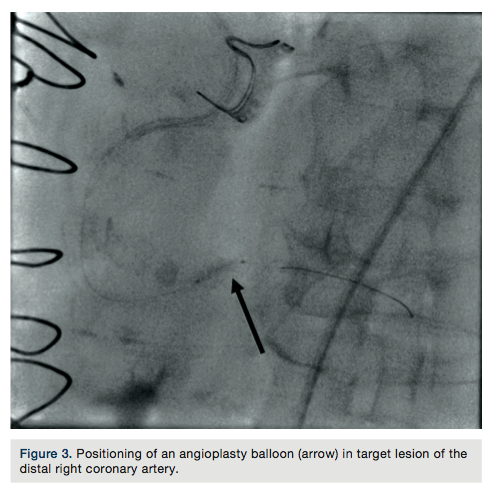

A 75-year-old female with a past medical history of coronary artery disease with previous coronary artery bypass grafting with left internal mammary artery (LIMA) to left anterior descending (LAD) artery, saphenous venous graft (SVG) to ostial medial (OM) branch, SVG to postero-lateral (PL) branch, and bioprosthetic aortic valve replacement presented with progressive dyspnea on exertion associated with substernal chest pressure. She presented with no ECG changes or elevation in cardiac biomarkers. Despite optimal medical management, she continued to endorse chest pain and thus underwent cardiac catheterization for evaluation of her coronary anatomy. Catheterization revealed a patent LIMA to LAD and SVG to OM, moderate disease in the SVG to PL graft, and a new, severe subtotal occlusion of the posterior descending artery (PDA) from the right coronary artery. We proceeded with intervention to this vessel using a 6 French (Fr) 0.75 Amplatz guide catheter. The index lesion was crossed with a Balance Middle Weight (BMW) guide wire (Abbott Vascular), with difficulty. Predilation was attempted with a 2.5 x 12 mm Apex balloon (Boston Scientific), but could not be advanced beyond the mid PDA. A GuideLiner catheter (Vascular Solutions) and a 1.25 x 10mm Sprinter Legend balloon (Medtronic) were advanced to the distal right coronary artery where they became resistant to advancement. The balloon was briefly inflated, but would still not advance. It was noted to have ruptured and despite aggressive tugging and pushing, could not be removed. The GuideLiner catheter could not be advanced further into the vessel to help free the balloon. It could also not be removed entirely, as it contained the shaft of the balloon. Eventually, with applied tension, the balloon shaft avulsed and remained in the distal RCA. Two different snares and two QuickCross catheters (Spectranetics) were advanced over the guide wire, but could not reach the site of the balloon. Given the tortuous anatomy and degree of calcification, it was determined that no other device or stent could be delivered, and thus the delivery wire was removed. Final angiography revealed TIMI-3 antegrade flow into the PDA, but with an obvious retained balloon tip and associated filling defect. Severe residual stenosis of the index lesion also remained. The patient remained hemodynamically stable throughout the procedure and asymptomatic subsequently. No ECG changes were identified and no regional wall motion abnormalities were seen on